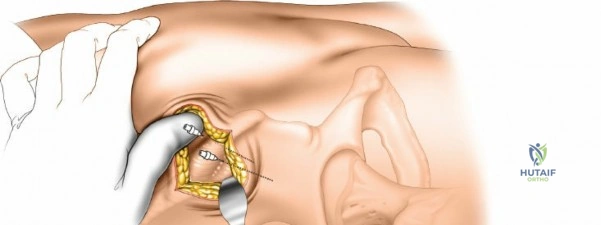

The fundamental technique for pin insertion remains consistent across all anatomical regions to minimize complications. Skin incisions for pin insertion must be longitudinal and generous enough to prevent skin tension against the pin. After the skin incision, blunt dissection using a curved hemostat is performed down to the periosteum. A tissue protection sleeve and trocar are inserted. The bone is pre-drilled using a sharp drill bit to prevent thermal necrosis, which is a primary cause of early pin loosening and infection. The pin is then inserted manually or under power at low speed, ensuring bicortical purchase.

External fixation of the radial diaphysis requires meticulous attention to the superficial radial nerve and the posterior interosseous nerve.

Mid-to-Proximal Radius Pin Placement

1. Supinate the forearm to move the PIN dorsally and radially.

2. Make an incision over the dorsolateral aspect of the radius.

3. Dissect between the extensor carpi radialis brevis (ECRB) and the extensor digitorum communis (EDC).

4. Use retractors to carefully protect the PIN.

5. Insert the tissue sleeve, pre-drill, and place a 4.0 mm pin bicortically.